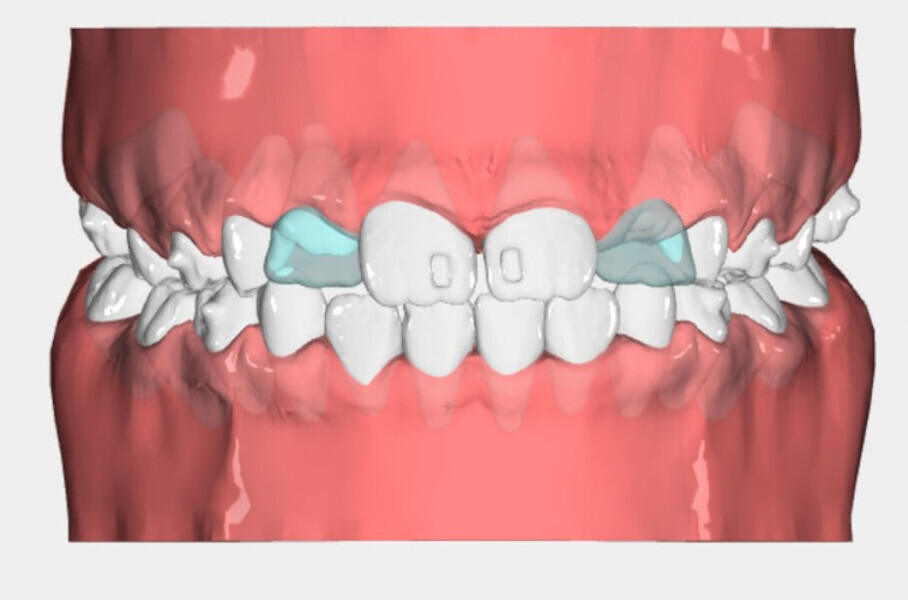

After 18 months of therapy, a case reassessment was carried out to verify that the goals had all been achieved (Fig. 8). Comparison of extra-oral photographs at the start of treatment (T0) and end of treatment (T1; Fig. 9) showed that excellent balance of the patient’s face had been achieved with a regular, symmetrical smile. Comparison of the intra-oral photographs (Fig. 10) and models (Fig. 11) also showed wider and more harmonious arch forms, closure of the anterior diastema, closure of the open bite and recentring of the mandibular midline. Excellent gingival trophism had also appeared.

Analysis of the models in Autodesk Netfabb software (Fig. 12) showed regularisation of the arches and an increase in the maxillary inter-canine diameter of 2.61 mm and in the maxillary intermolar diameter of 2.29 mm. The superimposition of the arches at T0 and T1 (Fig. 13), performed using OnyxCeph3 (Image Instruments), was very significant and showed the shift from the initial arch shape and size to a wider shape posteriorly but with significant control of the maxillary incisor area.